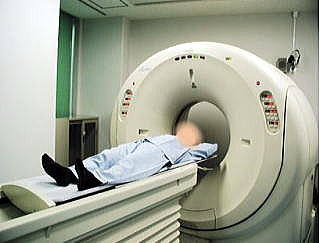

下はグーグルマップで見た慈恵医科大学付属病院の位置(東京都港区西新橋)。この病院は東京の中心(都心三区のさらに中心)にあり、芸能人、スポーツ選手、著名政治家などが入院するので有名。実際、私が入院した個室の並びにもそれらしきひとが入院していた。 ただし、私の自宅(東京都品川区小山)からは都営三田線一本、15分程度でこれ、車でも20数分でこれる。 また外来は早朝から大混雑しており、関係者は3-4時間待ちが普通であると言っていた。私が外来で検査に来た日も混雑しており、B1の脳神経外科で実質2時間以上待たされた。 大きな地図で見る こうして、私は第二頸椎を骨折しつつも、当面、何とか命拾いすることになる。 だが、このままほっておくといつなんどき下半身不随さらに頓死するか分からないという。また第二頸椎が折れているので、頭や首を動かすとき、とくに寝るときなどは当然ながら激痛が走る。 そこでに2010年11月11日、慈恵医大付属病院の神経系外科で外来検査を受けた後、その場で緊急入院することになった。病床がいっぱいだったので、とりあえず救急車などで運び込まれる救急センターの病棟に一泊し、その後、中央病棟の16階の個室に移動することになった。 11月11日の外来当日の検査としては、CT撮影、頸椎レントゲン撮影、心電図、尿採取検査、血液採取検査、呼吸器機能検査、血中酸素飽和度検査、血圧測定、血糖値・ヘモグロビン測定、脈拍数、体温測定などであるが、入院後はさらに多くの検査を毎日受けるはめになった。まさに検査漬けである。 ◆CT検査、MRI検査、レントゲン検査 下は旗の台脳神経外科及び慈恵医大付属病院で頸椎骨折を確認するために使ったCT及びMRIと同じものである。 CT断層撮影装置。初動の脳神経外科で1回、慈恵医大病院で術前術後を含め5回、さらに手術では慈恵医大脳神経外科だけに導入されているという手術中随時CTが撮影でデジタル録画され後に検証データとして使えるシステムも使った。  CT検査(イメージ図)